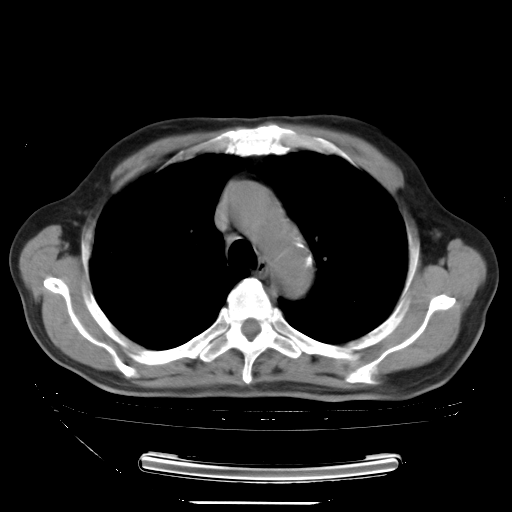

今天复查肺部CT,发现双肺广泛磨玻璃样改变。所以我把3月19日和5月9日相隔50天的肺部CT上传。请大家会诊。

2009年3月19日肺部CT片。

2009年3月19日肺部CT